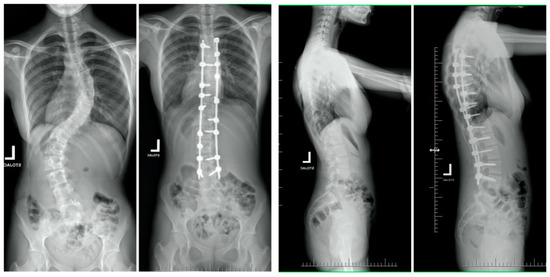

| Mean (SD) preoperative Cobb, deg | 131 (13.8) | 60 (9.5) | <0.001 |

| Mean (SD) Cobb at final follow-up, deg p-value * (pre vs. follow-up) | 61 (19.2) | 18 (9.2) | <0.001 |

| Mean (SD) preoperative thoracic kyphosis T5-T12, deg | 83 (35.9) | 25 (14.2) | <0.001 |

| Mean (SD) thoracic kyphosis T5-T12 at final follow-up, deg p-value * (pre vs. follow-up) | 35 (9.6) | 22 (8.2) | 0.24 |

| Mean (SD) preoperative forced vital capacity, percentage of predicted | 51.2 (12.8) | 83 (11.2) | <0.001 |

| Mean (SD) forced vital capacity, percentage of predicted at final follow-up p-value * (pre vs. follow-up) | 69.9 (11.2) | 79 (13.2) | 0.486 |

| Mean (SD) preoperative forced expiratory volume in one second, percentage of predicted | 60.8 (13.9) | 77 (12.8) | <0.001 |

| Mean (SD) forced expiratory volume in one second, percentage of predicted at final follow-up p-value * (pre vs. follow-up) | 76.9 (14.5) | 81 (12.8) | 0.282 |